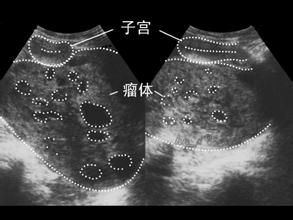

流行病學 病因 發病機制 臨床表現 併發症卵黃囊瘤(yolk sac tumor)是卵巢惡性生殖細胞瘤(OGCT)中最常見的一種腫瘤。世界衛生組織(WHO)在卵巢腫瘤分類中將原通用名卵巢內胚竇瘤...

概述 發病機制 臨床表現 診斷 檢查卵巢黃素瘤,多見於葡萄胎或絨毛膜癌。它是由於大量絨毛膜促性腺激素刺激卵泡而引起。腫瘤體積大小不一,大者直徑可達10~15厘米,甚至更大。腫瘤內含清亮液體...